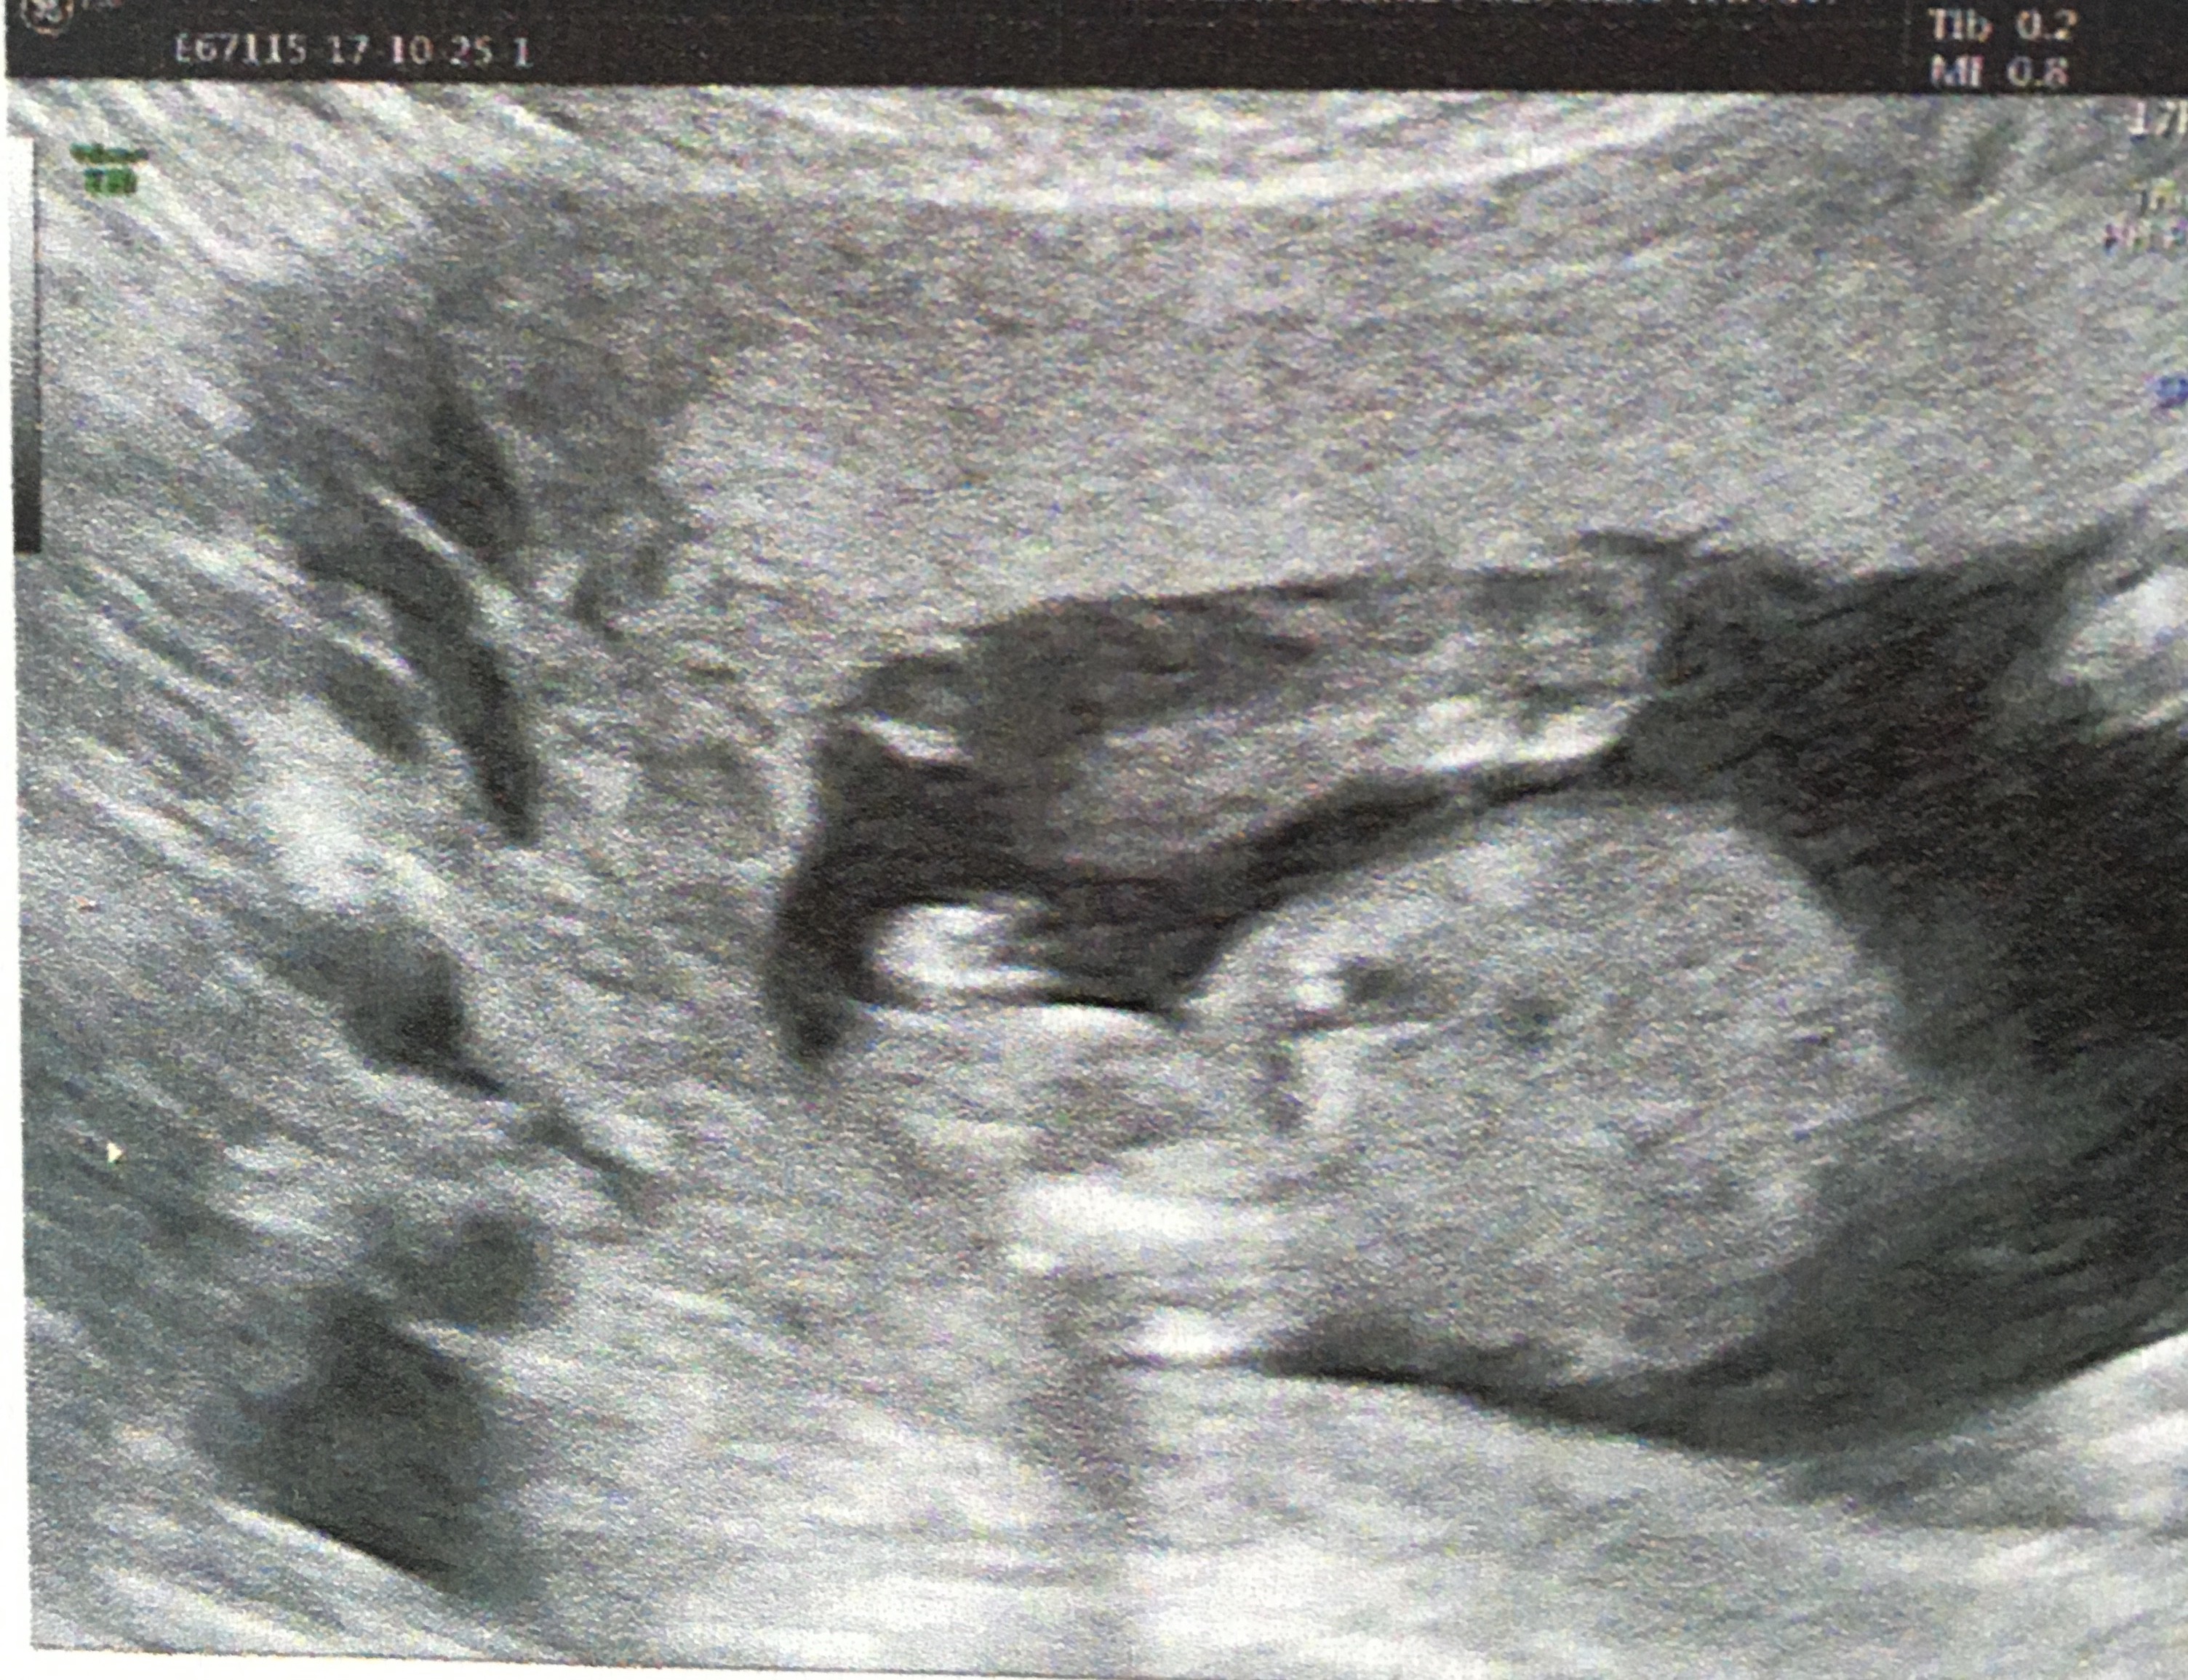

Get premium, high resolution news photos at Getty ImagesL' échographie des 12 semaines Au cours de cet examen, le médecin scrute les différents organes, notamment le tubercule génital Un certain nombre de travaux ont démontréSi le tubercule est perpendiculaire au corps alors c'est probablement un garçon!

Partir du tubercule génital avant 12 SA car le taux d'erreur est de 40 % et donc ne dépasse que de peu l'effet du hasard l'aspect est dit féminin quand le le tubercule génital part vers le bas et horizontalement l'aspect est dit masculin quand le tubercule génital part en avant etFille ou garçon tout se décide lors de la fécondation, au moment même oùDès le début ou plutôt dès la première échographie celle qui se fait vers 12 SA et qui est généralement la première si tu n'as pas eu d'échographie de datation, parce que t'es en impatiente, parce que tu veux commencer à

C'est parce que le tubercule génital commence àNous laisser un message àL'angle du tubercule génital masculin a une angulation de 30º

L'échographie de grossesse, bon passage des ultrasons àQuels risques de contamination ?Si le tubercule est dans l'axe du corps il y a des chances que cela soit une fille!